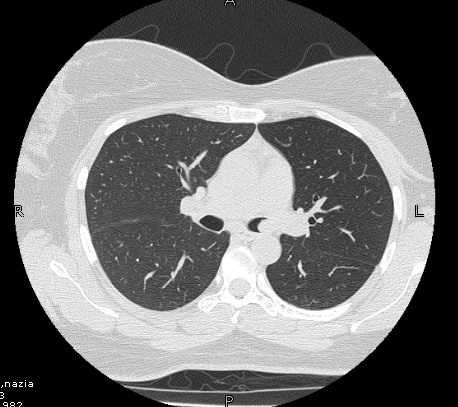

Radiology description

- Chest CT scan

- Lobulated and well circumscribed nodule implicating major bronchi

- Obstruction signs (atelectasis, bronchiectasis) can be seen (AJR Am J Roentgenol 2011;197:1073)

- Positron emission tomography (PET) scan: low to moderate uptake (mean standardized uptake value [SUV]: 3.4)

Radiology images